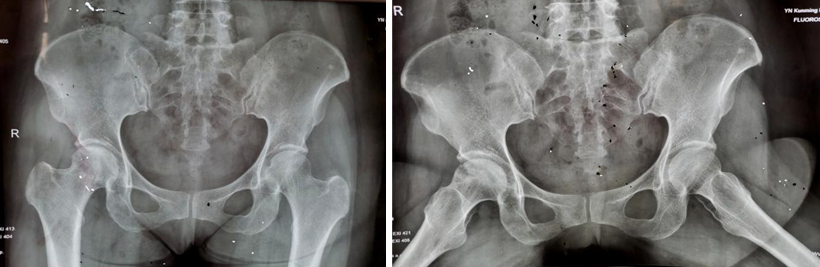

两年多前,34岁的王先生因双髋部疼痛伴活动受限4月余,在家人的搀扶下,一脸痛苦地来到亚洲色吧 骨科就诊。杨振东副主任医师接诊了这位患者,该患者饮酒史10年,每日2两,戒酒1月,右髋外旋活动受限,左髋活动正常,右髋“4”字试验阳性,结合影像学资料显示,该患者右侧股骨头凹凸不平、黯淡无光,且有部分塌陷,诊断为右侧股骨头坏死。

入院3天后,杨振东医师为该患者进行了吻合血管的游离腓骨移植手术治疗。患者全麻生效后取右侧仰卧体位,杨振东医师先从患者身上取长约8CM带血管蒂骨,然后进行股骨头病灶彻底清除,最后截取合适长度游离腓骨,植入股骨颈内,吻合游离雕骨血管至旋股外侧动静脉。手术持续约6小时,手术顺利,患者复苏后安返病房。